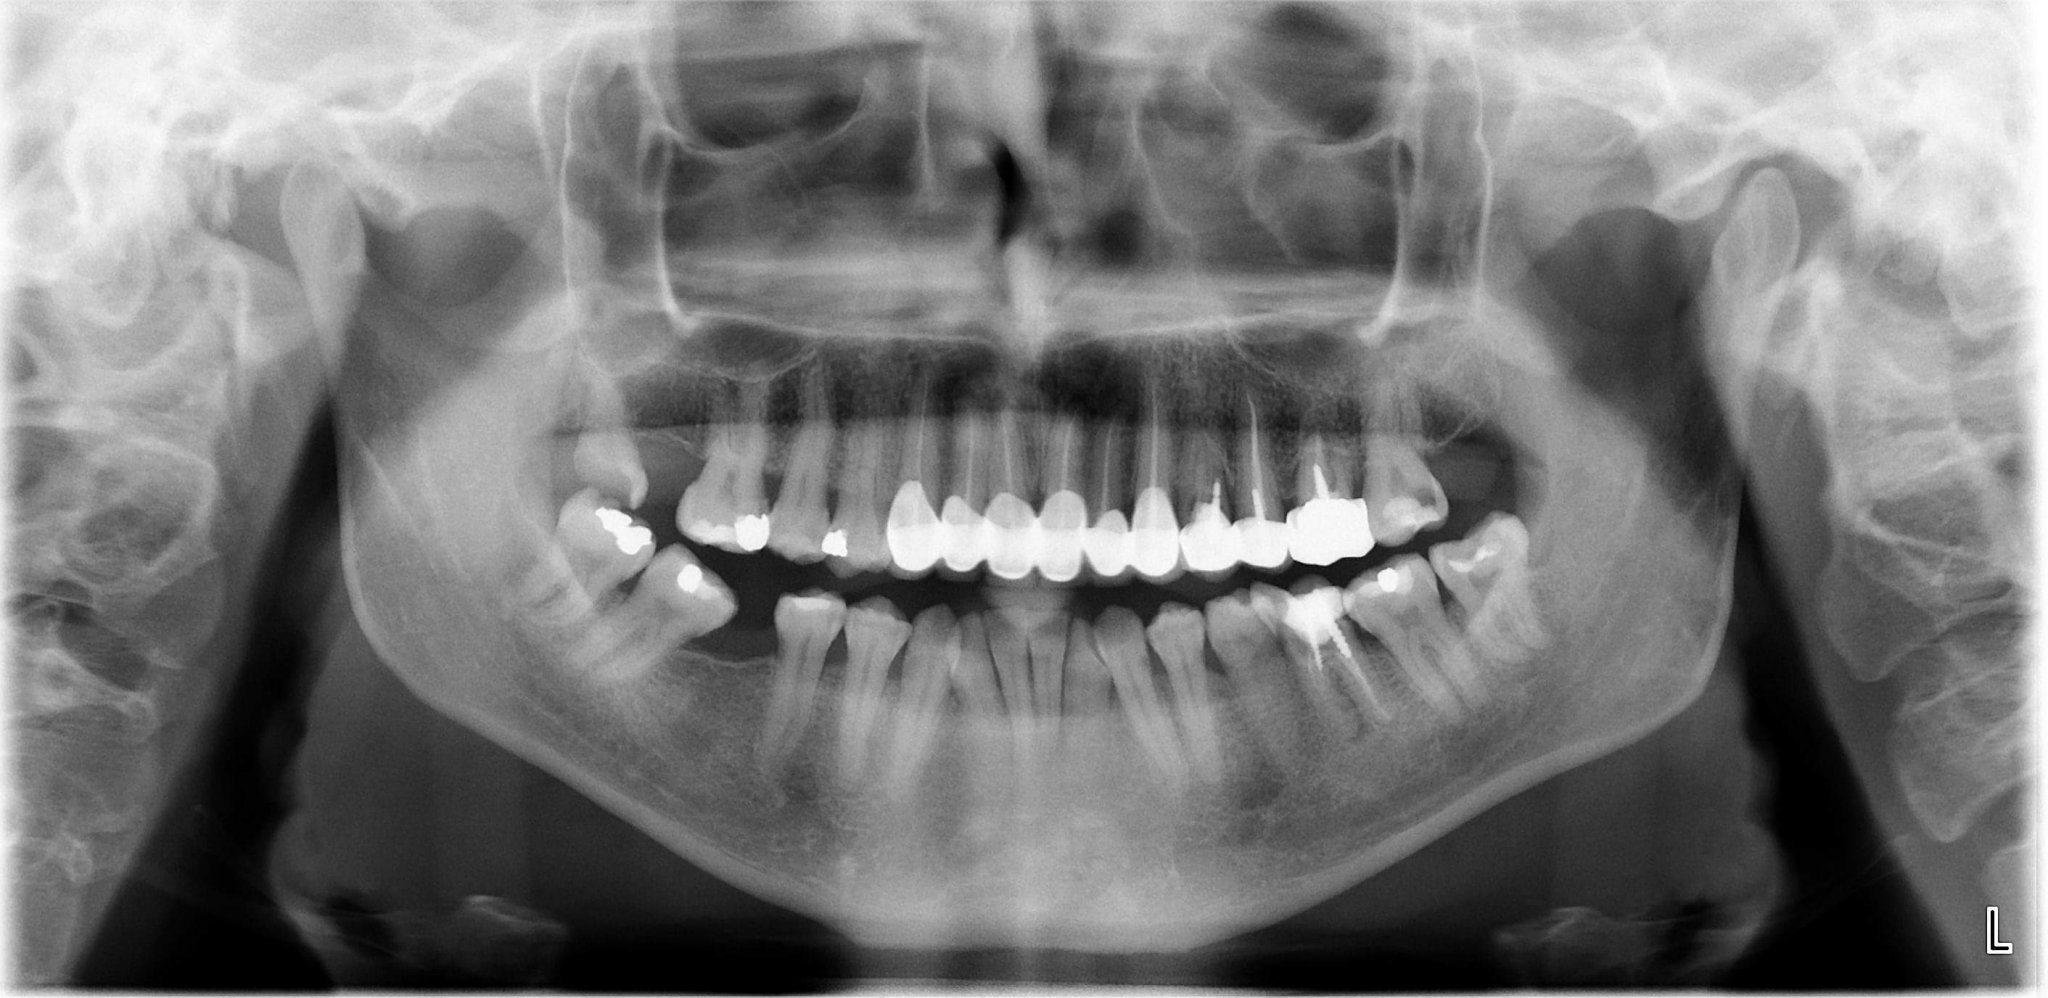

Здравейте!Нова съм в групата....Някой може ли да ми каже дали на панорамната ми снимка би имало нещо притеснително?Имам проблем в устната кухина от 7 месеца.От Русе съм и никой доктор неможе да ми каже какъв ми е проблема.Подуват ми се горните венци.Езилът ми е все едно на пъпки или може би са просто възпалени напиши,от което се появява и постоянен лош дъх...

Зависи колко е стопена и до къде. Има снимки и се вижда. Може да е в начална фаза, може и да е в крайна!